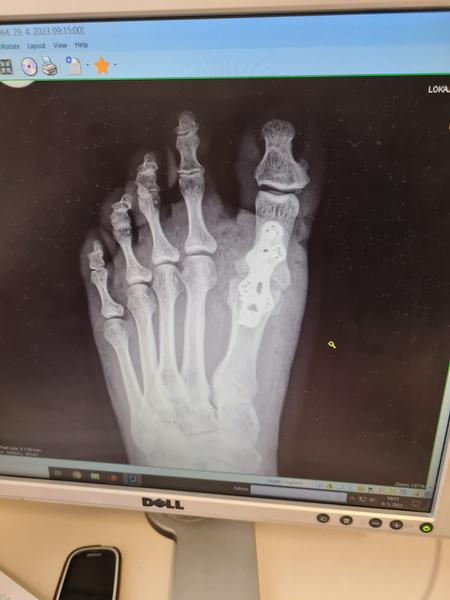

@adrianadeutschova to máš celkom peknú jazvicku., ja som mala takuto,mam tam platničky,aj sroby

@adrianadeutschova ale mne robili artrodezu..na konci apríla...uz je to fajn..

Mam dva sroby v palci a tie prsty nejako prepilovali aby sa upravila aj klenba a viem, ze rozmýšľali, ze tam dajú také kovové tyčky ale ci tu tam alebo nie, tak to neviem.